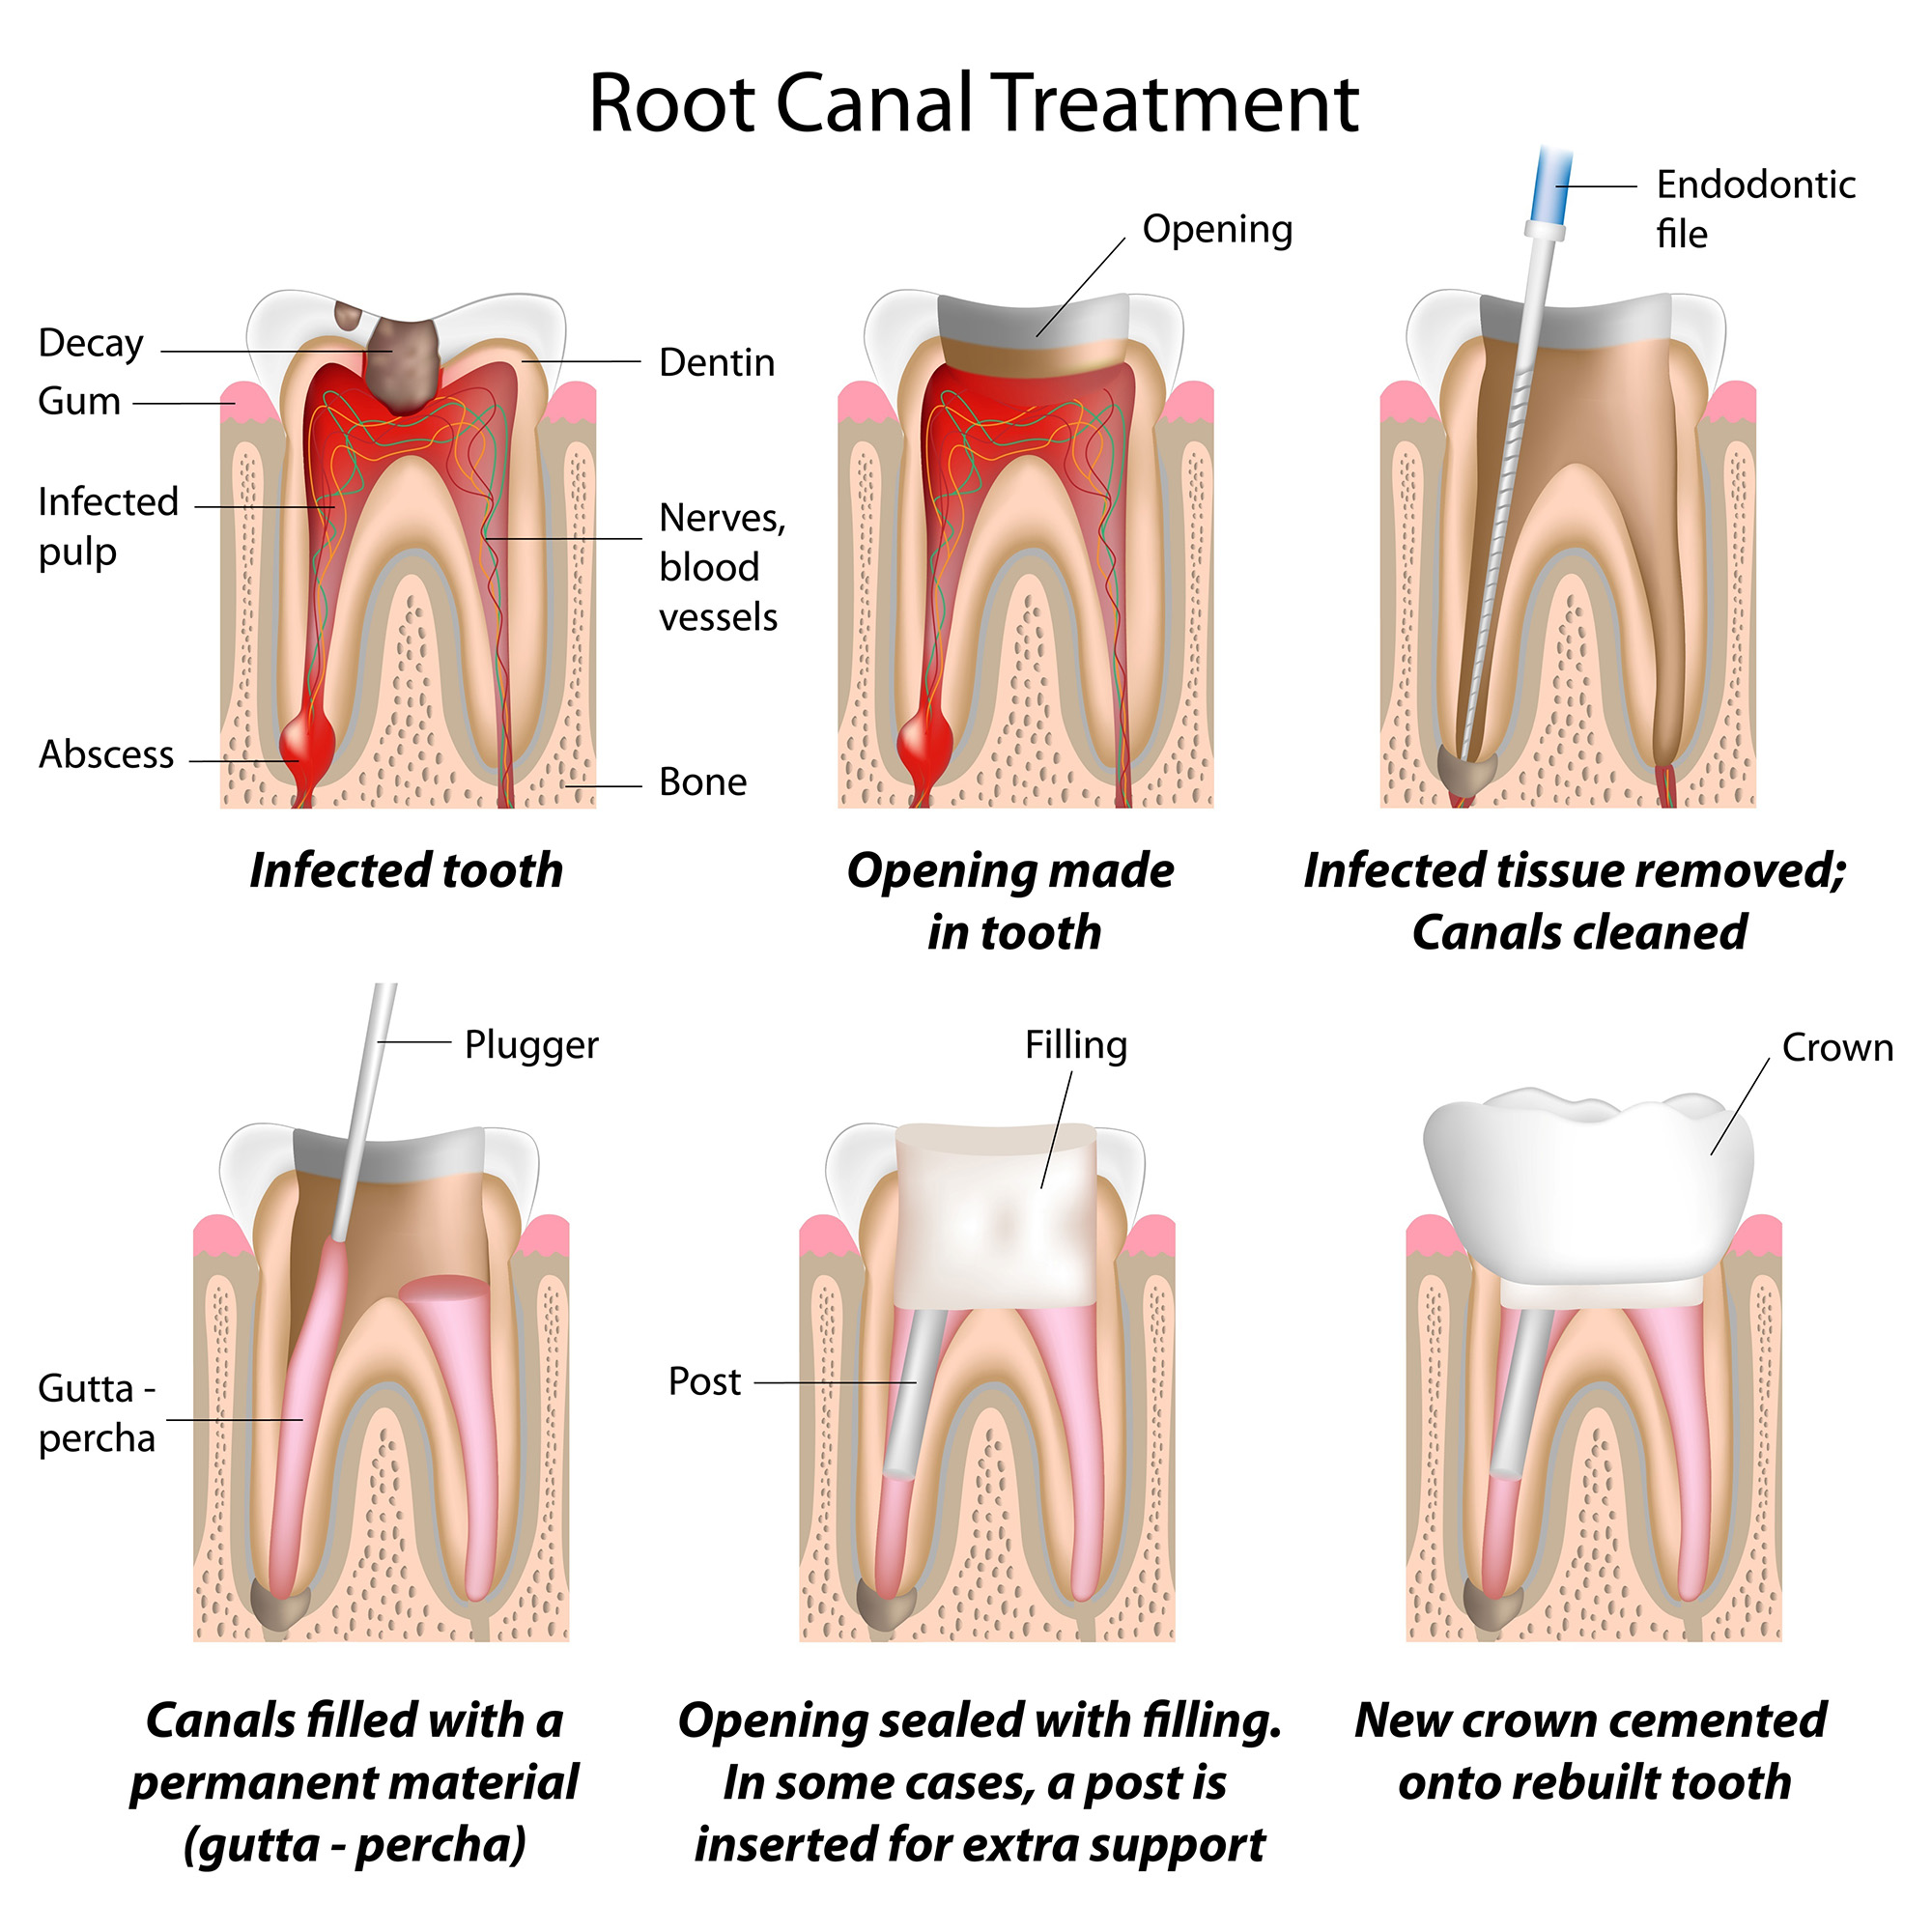

Tratamiento endodóntico

No obstante, cuando la viabilidad de los tratamientos anteriormente mencionados resulta cuestionable, especialmente por un deterioro acusado del diente que implica una lesión directa sobre la pulpa o nervio, la endodoncia se perfila como la opción más adecuada. El objetivo final es la conservación del diente natural y su mantenimiento desde un punto de vista funcional. En algunos casos es necesario colocar algún tipo de refuerzo interno en la raíz, como los postes de vibra de vidrio. Una vez desinfectado el interior del diente, éste se rellena con un material especial, la gutapercha. Una anatomía compleja de las raíces (excesivamente curvas, excesivamente estrechas…) puede complicar el tratamiento. Si la endodoncia no produce la curación deseada, puede estar indicado el retratamiento (reendodoncia) o complementarlo incluso con un abordaje quirúrgico (la apiceptomía).

Debemos destacar que los dientes endodonciados, por defecto, quedan debilitados como consecuencia de toda la estructura dental que se elimina para su restauración, existiendo entonces cierto riesgo de fractura de la raíz. De darse el caso, la extracción dental sería única alternativa posible de tratamiento.